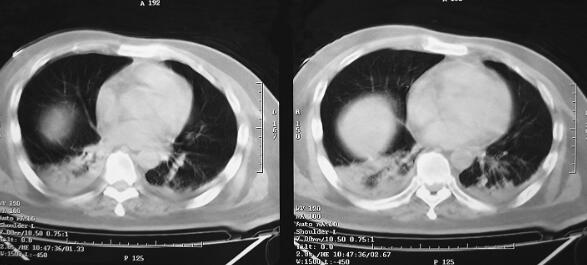

诊治经过:患者入笔者科室后一般情况较差,血压测不出,氧饱和度84%,予以羟乙基淀粉扩容,多巴胺、去甲肾上腺素微泵维持血压,碳酸氢钠纠正酸中毒。立即予以气管插管,呼吸机辅助通气。完善相关检查:CT(图1)结果:①头颅CT平扫未见明显异常;②双下肺肺不张;③双侧胸腔积液;④肝右叶钙化灶。血常规(2月7日):WBC 20.9×109/L,N 94%。心脏彩超(2月8日):左心室舒张末内径61mm,射血分数38%。胸片(图2~图4)诊断:①双侧肺炎;②颈椎术后。先后给予头孢曲松钠和左氧氟沙星、美罗培南和替考拉宁抗感染。因痰培养鲍曼不动杆菌(2月10日),对头孢哌酮-舒巴坦钠敏感,余均耐药,故停用美罗培南,改用头孢哌酮-舒巴坦钠。多次血培养结果提示白念珠菌(2月6日、2月7日、2月9日、2月10日),对氟康唑和伊曲康唑均敏感,因为患者肌酐高,肾功能异常,故给予米卡芬净和氟康唑抗真菌治疗。患者血糖高,2月6日末梢血血糖33.1mmol/L,给予胰岛素强化治疗,但是血糖控制不佳,一直在11mmol/L以上。同时给予化痰、抗炎、保肝、营养神经、调节机体免疫、加强营养、维持内环境稳定、对症支持等治疗。

图2 2月9日胸片